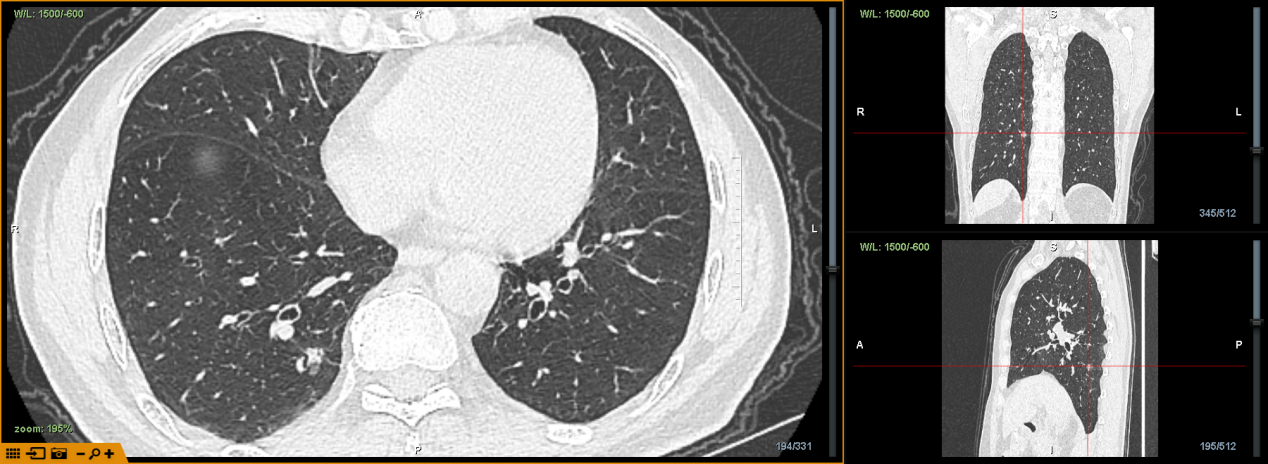

据介绍,该患者为70岁男性,由于体检时发现肺部结节2周,建议做进一步治疗,于3月收入中南大学湘雅三医院心胸外科。经胸部CT显示检查发现,该患者右肺下叶结节影,不能排除恶性,遂建议进行进一步手术。

图一:患者CT影像

术前,通过导航系统对患者进行CT三维重建规划,评估分析,患者病灶位于右肺下叶后基底段,大小约10mm*9mm,距离胸膜有一定距离。为精准定位肺结节,明确切除范围,同时尽可能保留正常肺组织,金龙玉教授团队决定应用增强现实光学导航系统引导下,在气道内使用一次性使用肺外科H-Marker金属标记物定位肺结节,行胸腔镜下微创肺结节切除术。